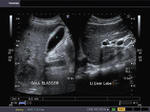

Riedel's lobe of liver

The above ultrasound images show what appears to be right renal lower pole mass (image in top row left). But further ultrasound imaging of the liver shows it to be an extension of the right lobe draped over the anterior surface of the right kidney. The apparent mass (M) appears to be on the tip of the tongue of liver tissue. This beak of liver tissue extending from the right lobe of liver is called Riedel's lobe of the liver and is a very rare normal variant. This patient was referred to a CT imaging center for further evaluation of the suspected mass in the tip of the Riedel's lobe. The sketch in bottom row-Right shows detailed anatomy of the Riedel's lobe. The gall bladder was visualized and appeared normal.